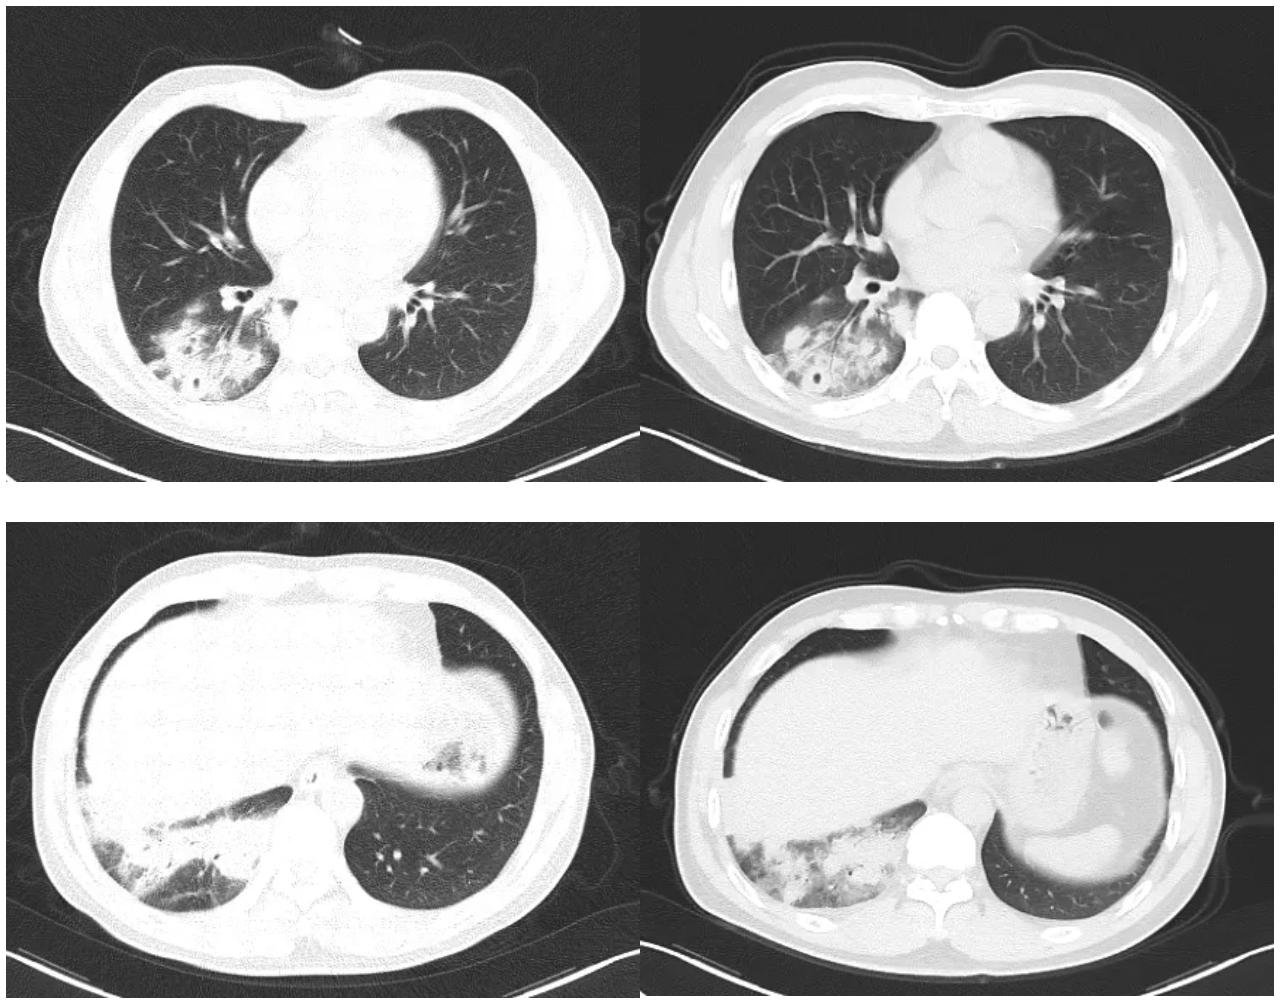

抗感染治疗7天后,患者未再出现痰中带血,但咳嗽、胸闷症状无明显缓解。 复查胸部CT较院外旧片比进展 (图2)。

图2:胸部CT示右下肺炎症,可见空洞形成。

综合分析原因有两种可能性,一是抗生素未覆盖致病菌,二是非细菌感染或者非感染性疾病所致。但考虑患者生命体征平稳,未升级抗生素,而是进一步寻找病因:完善纤维支气管镜检查,镜下见气管及各级支气管粘膜光滑,管腔通畅,可见少量粘稠分泌物,抽取分泌物送细菌培养,并0.9%生理盐水灌洗右下叶背段支气管,留取灌洗液送检真菌GM试验、抗酸染色、弱抗酸染色、真菌涂片及病原学mNGS,于7组淋巴结行EBUS-TBNA,于右下叶后基底段支气管行EBUS-TBLB。结果回示真菌GM试验、抗酸染色、弱抗酸染色、真菌涂片均阴性;7组淋巴结穿刺细胞块病理回示渗出背景上少量淋巴细胞,右下叶TBLB肺活检示肉芽肿性炎(图3),抗酸染色(-),PAS(-),六胺银(-),TB-DNA(-)。

在此阶段,我们修正诊断后,加用了氟康唑400mg/d抗隐球菌治疗。治疗3天后患者咳嗽、胸闷症状出现明显缓解,治疗8天后复查胸部CT示右肺下叶炎症较前稍减轻,右侧少量胸腔积液较前减少(图5)。

图5:氟康唑治疗8天后胸部CT对比,左侧为治疗前,右侧为治疗后